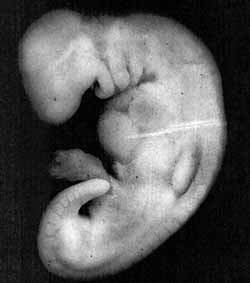

Illustration 4: Diagramme du système cardio-vasculaire rudimentaire d'un embryon au stade de la alaqah. L'apparence externe de l'embryon et de ses sacs est similaire à celle d'un caillot de sang; cela est dû à la présence de grandes quantités de sang dans l'embryon. (The Developing Human [L'humain en développement], Moore, 5e édition., p. 65.)

Ainsi, les trois sens du mot alaqah correspondent exactement aux descriptions de l'embryon au stade de la alaqah.